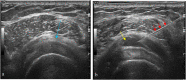

The rotator cuff is a group of four muscles and tendons surrounding the shoulder joint providing it strength and stability. The rotator cuff consists of the subscapularis, supraspinatus, infraspinatus and teres minor. Many shoulder complaints are caused by rotator cuff pathology such as impingement syndrome, tendon tears and other diseases e.g. calcific tendonitis. Diagnosis starts with clinical history and physical examination, after which imaging is often used to help confirm clinical findings depending on the differential diagnosis. The aim of the article is to review the frequently used imaging modalities to assess the rotator cuff and cuff-related disease, specifically focusing on radiography, ultrasonography and magnetic resonance imaging. This article will outline the advantages and disadvantages for each modality and illustrate typical radiological findings of common rotator cuff pathologies.